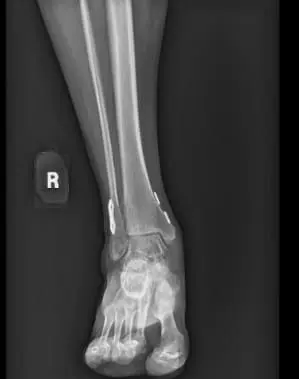

At his four-month follow-up, the patient was fully weight-bearing and had returned to work at full duty. He no longer required a brace and had full ankle stability with minimal pain. Follow-up X-rays showed complete healing with no hardware complications.